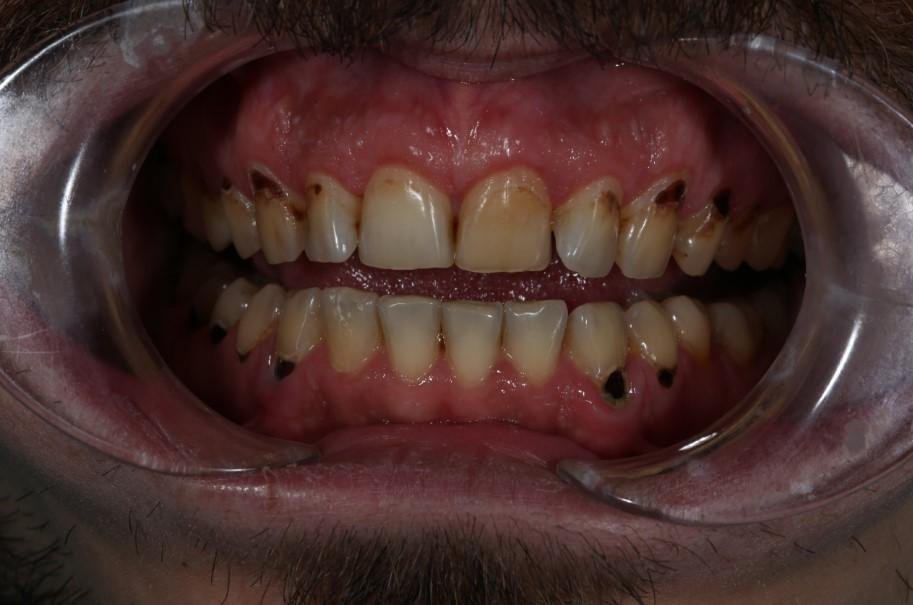

Как выглядел профиль пациента (фото)

Тут нужно пояснить. В норме площадь всех зубных контактов — 0,5-1 кв. см. При большей площади мозг передает в мышцы челюсти сигнал: сжимай зубы плотнее! При постоянном сжатии зубы стираются, обнажается дентин. Он менее крепок, чем эмаль, в нем всего 70% минеральных соединений. Обнажённый дентин уязвим перед кислотностью продуктов, поэтому зубы очень быстро разрушаются.

Третье – зубной камень и кариес. Это может говорить о любви к сладким перекусам с чашечной кофе – типичное питание айтишника. Дело в том, что кофе имеет кислую среду, что и создаёт тот самый дисбаланс в ротовой полости, из-за которого патогенные бактерии активно размножаются. Кстати, кофе имеет и обезвоживающий эффект, поэтому при его активном употреблении снижается количество слюны.